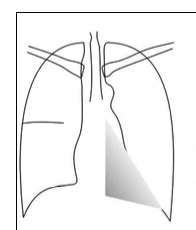

what does this show

LLL collapse